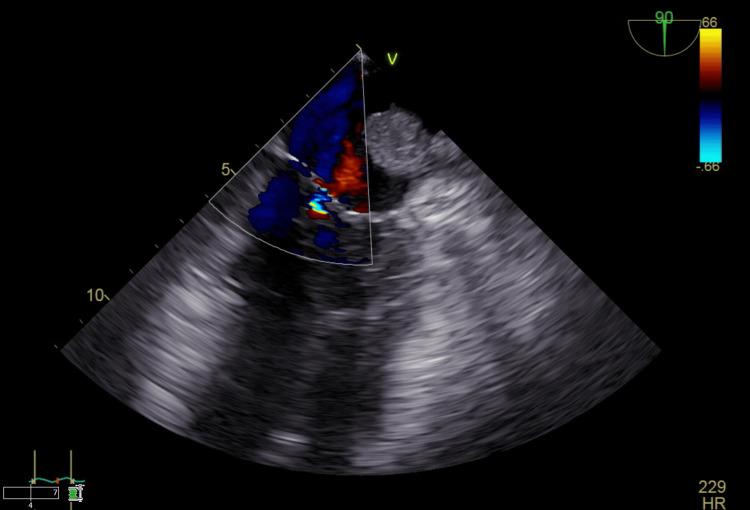

Infections of intracardiac thrombi are exceptionally rare but pose significant clinical risks, especially when located in the left atrial appendage (LAA). We present a unique case of a 51-year-old male with multiple comorbidities who was found to have an infected LAA thrombus causing persistent methicillin-resistant (MRSA) bacteremia and systemic symptoms. Initial presentation included altered mental status, diabetic ketoacidosis, and classic signs of endocarditis such as splinter hemorrhages. Transesophageal echocardiogram imaging revealed a thrombus in the LAA, which was later confirmed to be infected and was acting as a nidus for sepsis. Surgical intervention and targeted antibiotic therapy led to clinical improvement. This case highlights the need for heightened clinical suspicion and a multidisciplinary approach when managing unexplained bacteremia, particularly in patients with known thrombotic risk factors. It also underscores the rare but significant potential for cardiac thrombi to become secondarily infected, warranting further study into diagnostic and therapeutic strategies.

心内血栓感染极为罕见,但会带来重大临床风险,尤其是位于左心耳(LAA)时。我们报告了一例独特病例,一名51岁男性,患有多种合并症,发现其左心耳血栓感染,导致持续性耐甲氧西林金黄色葡萄球菌(MRSA)菌血症和全身症状。初始表现包括精神状态改变、糖尿病酮症酸中毒以及心内膜炎的典型体征,如瘀点出血。经食管超声心动图成像显示左心耳有血栓,后来证实已感染,并成为败血症的病灶。手术干预和针对性抗生素治疗使临床症状得到改善。该病例强调,在处理不明原因菌血症时,尤其是对于有已知血栓形成危险因素的患者,需要提高临床怀疑度并采取多学科方法。它还凸显了心脏血栓继发感染虽罕见但具有重大可能性,值得进一步研究诊断和治疗策略。